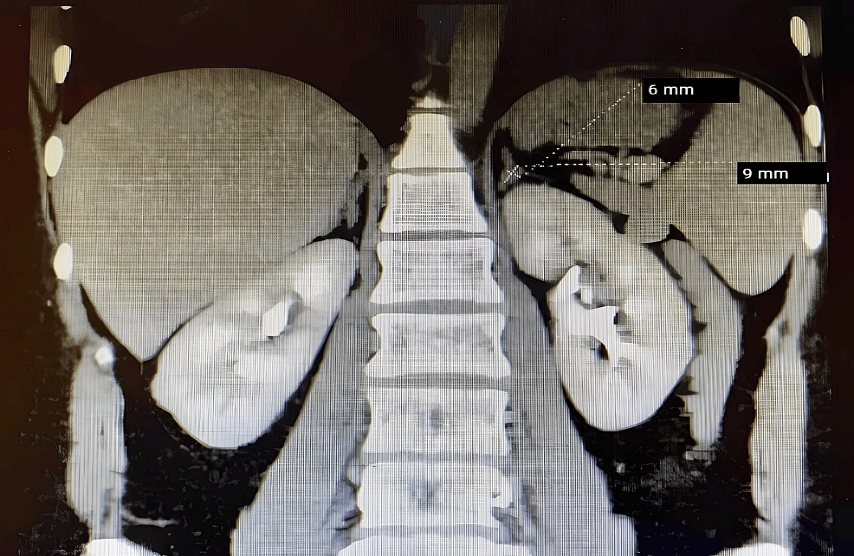

A CT scan of the abdomen with contrast revealed a small focal lesion (a left-sided adrenal mass) measuring approximately 9mm by 6mm on the left adrenal gland (Figure 1). The mass appeared to have a mostly homogenous contrast enhancement. Pattern and correlation with laboratory hormonal parameters were suggested for differentiation purposes, in conjunction with control CT scans.

Figure 1. Abdominal CT scan showing a homogeneous lesion, measuring approximately 9mm by 6mm on the left adrenal gland.